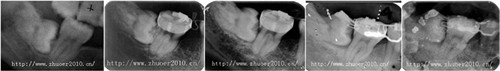

矫治前

矫治中

直立X线片

矫治前后X光片对比